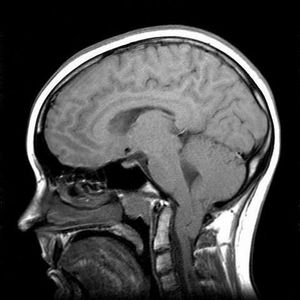

Chiari Malformation

Arnold Chiari Malformation 24mm in an 18yr old female. History of balance problems, nystagmus, pain and numbness down right arm.